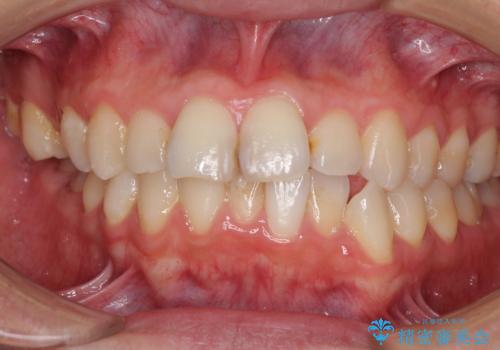

顎が左右にずれた咬み合わせ ハーフリンガルの抜歯矯正

- 口元の突出感を気にして来院された患者様です。

目立たない装置を希望され、上顎が裏側装置で下顎が表側装置のハーフリンガルを希望されました。

上下の顎骨が左右に大きくずれており、奥歯が交叉咬合となっていたため、ハーフリンガルよりも表側装置をおすすめしましたが、目立たない装置を強く希望されたため、治療期間が長期化することを前提に、ハーフリンガルにて抜歯矯正を行うこととしました。